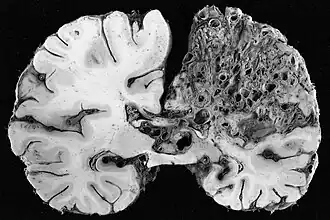

![]() Vista macroscópica de malformación arteriovenosa en el lóbulo parietal. | ||

La malformación arteriovenosa cerebral o MAV es una patología vascular congénita. Se trata de arterias anormalmente dilatadas que desembocan directamente en venas también anómalas (arterializadas), sin la interposición normal de una red capilar entre ellas,[1] sustituyéndose al capilar por un ovillo enmarañado de vasos sanguíneos irreconocibles; por lo que el paso de sangre desde la arteria a la vena se hace de una manera muy veloz, haciendo que la vena se dilate y corra el riesgo de romperse. Tienen el aspecto de una masa retorcida de tamaño anormal y un color grisáceo. Son lesiones muy poco comunes, ya que ocurren en menos del 1% de la población (3 de cada 10000 personas). Se presenta más comúnmente entre los 15 y 20 años, aunque también puede manifestarse posteriormente.[2]